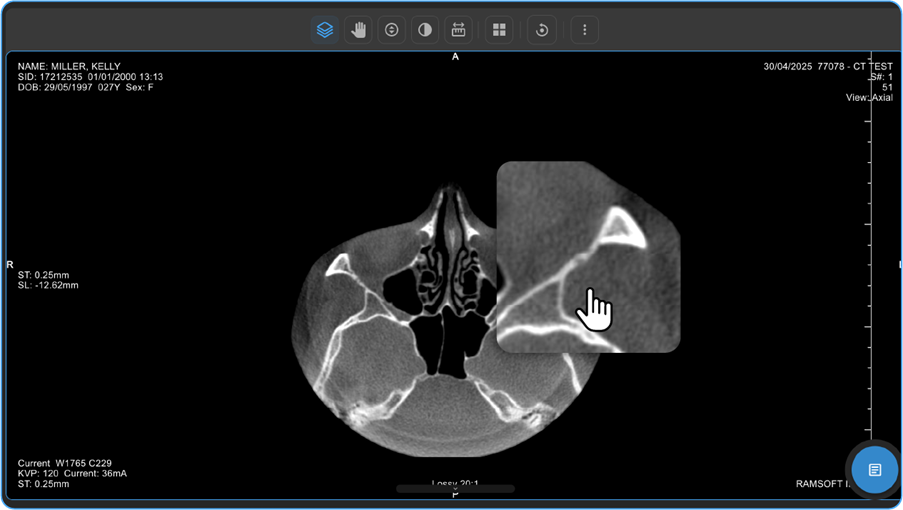

F. Focus on Specific Image Areas

1. Locate the Shutter Rectangle feature on the Adjustment wheel to mask unnecessary areas and highlight specific regions for better diagnostic efficiency.

vai

1. Alternatively, press F6 on your keyboard while the adjustment wheel is open to activate the Shutter tool.

2. Left-click and drag on the image to draw a rectangle over the area you wish to focus on.

1. The selected region will remain visible, while the surrounding areas are masked.

2. Additional Shutter Options- After activating the Shutter tool, left-click once to access different shutter shapes:

• Rectangle Shutter: Masks the area outside the drawn rectangle.

• Circle Shutter: Masks the area outside a drawn circle.

• Freehand Shutter: Allows you to draw a custom shape to mask specific areas.